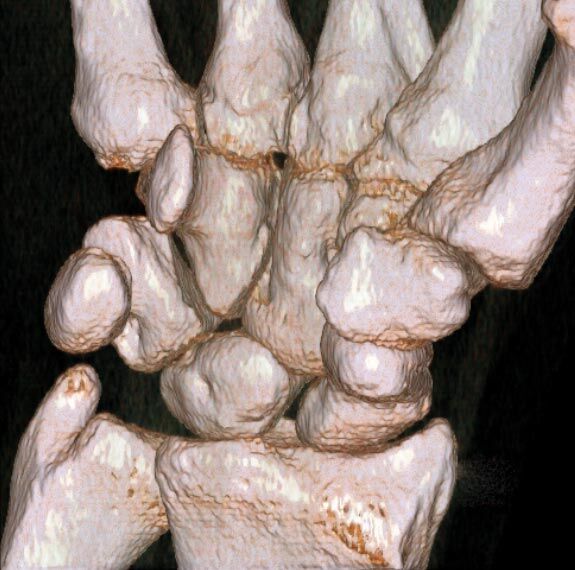

Extremitäten

• bei komplizierten Frakturen z. B. in der Nähe von Gelenken oder im Bereich der Handwurzel und Fußwurzel

• besonders hochauflösende, strahlendosissparende Darstellung aller Skelettstrukturen